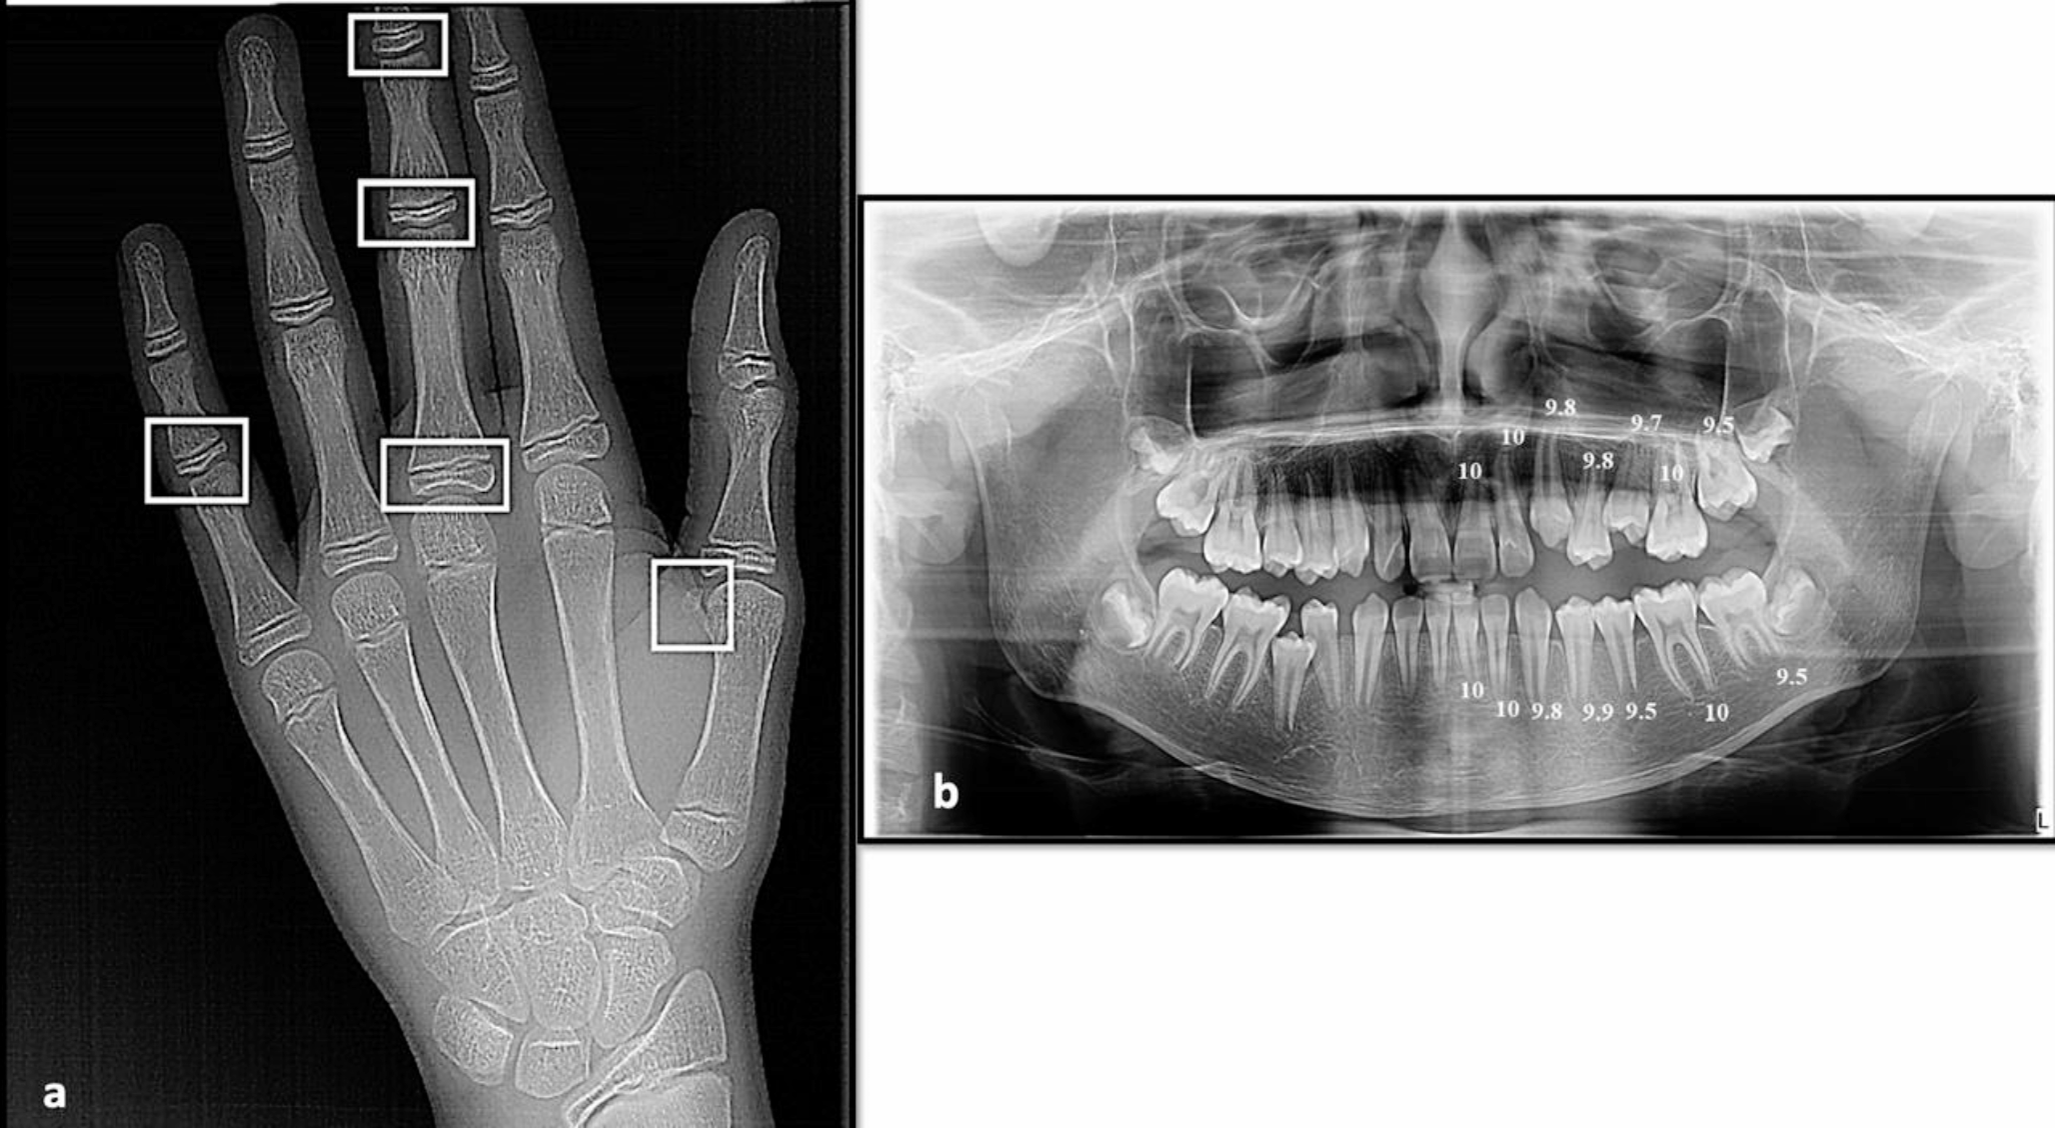

Fig. 3

a) Hand-wrist X-ray of a 14.98-year male patient showing different sites (in white) of skeletal maturity indicators (SMI) assessed by Fishman method; capping of epiphyses of the middle phalanx on the fifth finger (SMI = 7), and skeletal age is 14.43 years, b) Panoramic X-ray of the same patient showing different scoring of dental development of the mandibular and maxillary teeth on the left side (except the third molar), marked according to the Nolla method; the total scoring was 137.5 and the calculated dental age was 14 years

Bild vergrößern